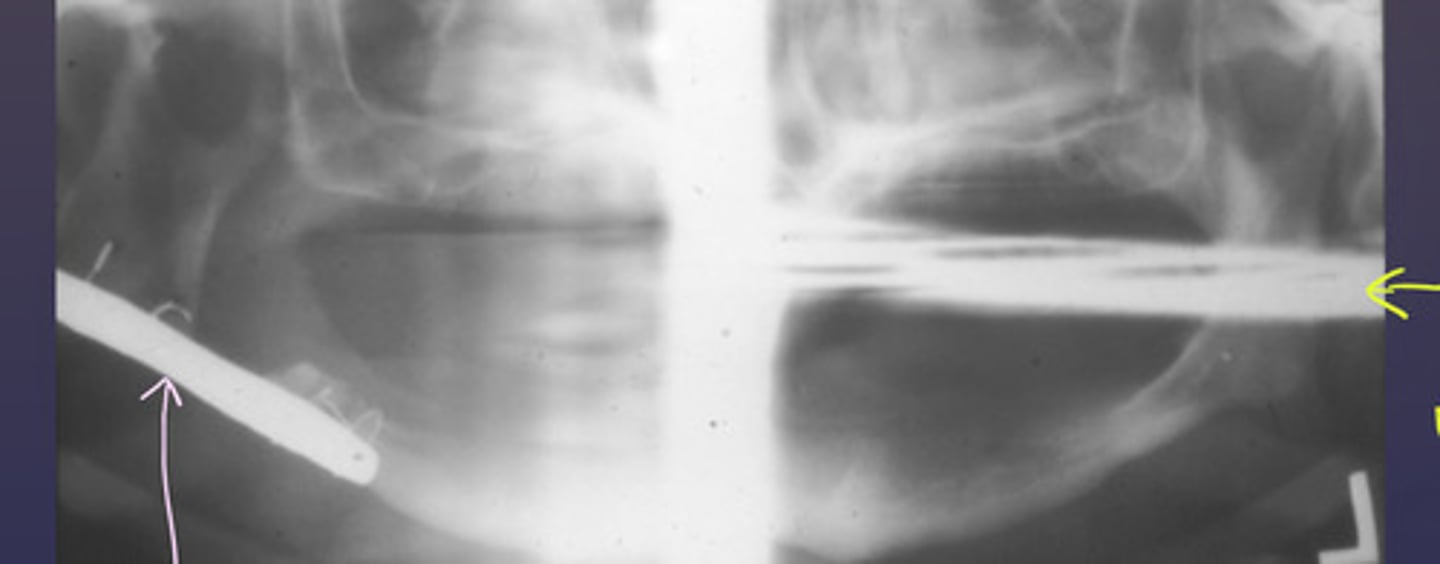

the following patient has a surgical plate. What type of image is the purple arrow pointing to?

real image

the blue arrow is pointing to what type of image of the cervical vertebrae?

ghost image